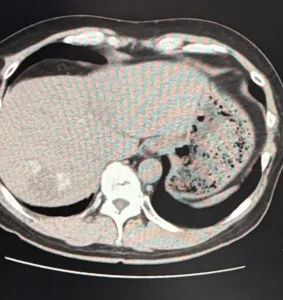

原因が分からないので、痛み止めを処方してもらって経過観察になりました。この時のCT画像では、がんが白く石灰化しているのが確認できました。

(腫瘍マーカー7)

腫瘍マーカーは7。ついにひと桁まで下がりました。抗がん剤治療の効果が出ています。